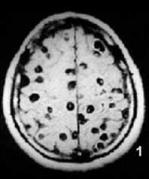

キムチの寄生虫、有鉤条虫(ゆうこうじょうちゅう)に巣食われた脳

【事例】

神奈川県在住、21歳女性。焼き肉が好きでよく食べるが、生肉は食べない。

キムチが好きで、韓国産のキムチ漬けを購入し常食していた。

1ヶ月前から感冒様症状があり、左上肢のしびれと右上肢の筋力低下を感じ来院。

頭部CTスキャンでは脳内に計1~2cmの腫瘤陰影が、血液検査では好酸球の増多が認められた。

このため、寄生虫症を疑って抗体検査を行ったところ有鉤条虫に対する反応が陽性であった。

【感染リスク】

感染源としては、ヒトの糞便に出現する虫卵と豚肉内の幼虫の2種が考えられる。

前者は 虫のみの感染であるのに対し、後者は有鉤条虫の感染を伴う。

上記事例は前者の可能性が濃厚で、輸入キムチが有鉤条虫に汚染されていた可能性が疑われたが確証は得られなかった。予防法は食品の加熱処理。

【症状と診断】

幼虫が寄生する部位により、皮下腫瘤、石灰化(最も多い症状で、皮下あるいは筋肉内の寄生)、

痙攣、頭痛、めまい、運動麻痺(脳内寄生)、視力障害、嘔吐、失明(眼球内寄生)などの症状が出現する。